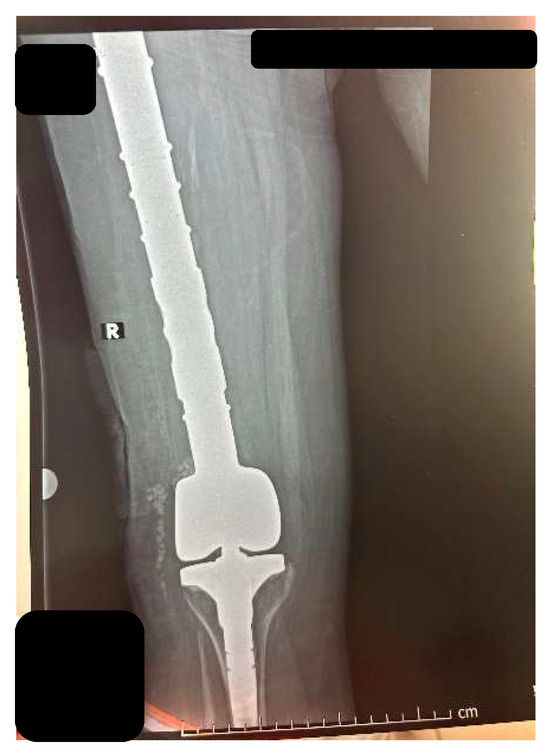

2.2. CASE 2